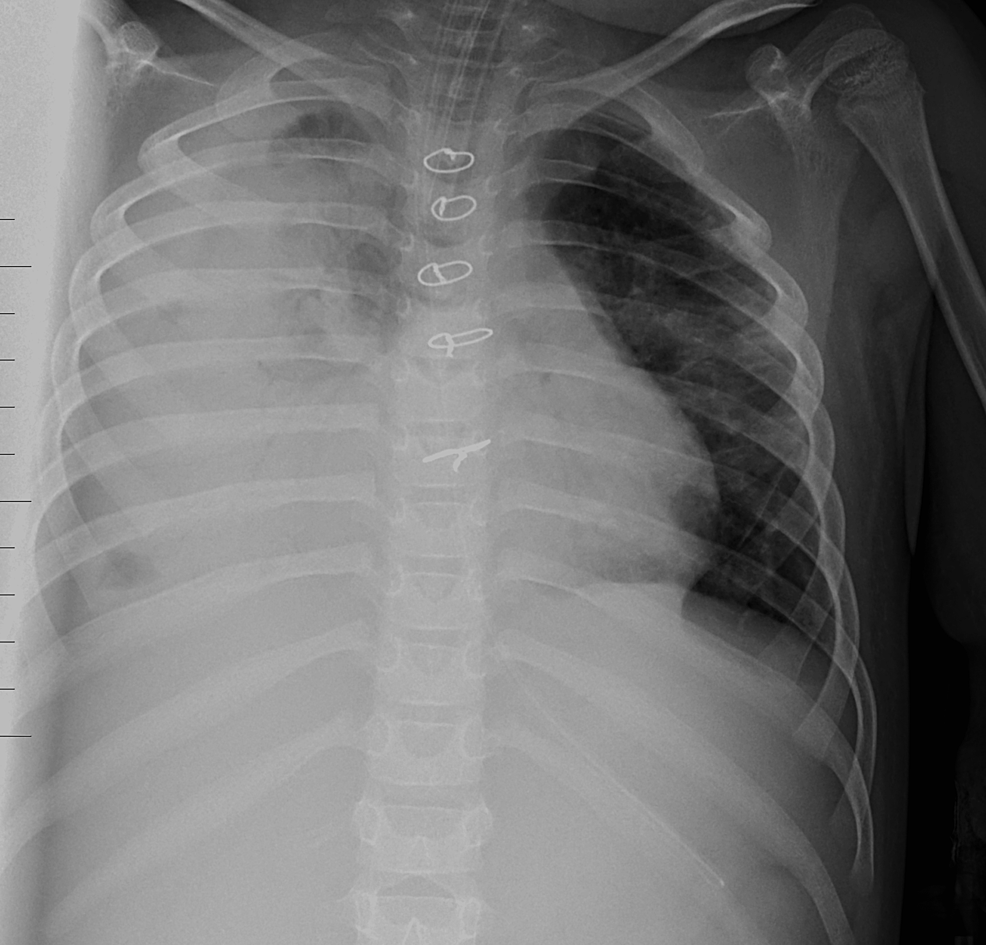

From www.cureus.com

Cureus Cystic Lung Changes in Down Syndrome A Case Report Does Vsd Mean Down Syndrome The hole occurs in the wall that. They vary greatly in location, clinical presentation, associated. But other heart defects are possible and can occur, including: Ventricular septal defects are the most common congenital heart defect. the most common heart defect in children with down syndrome is an atrioventricular septal defect (avsd), a large hole in the center of the. Does Vsd Mean Down Syndrome.